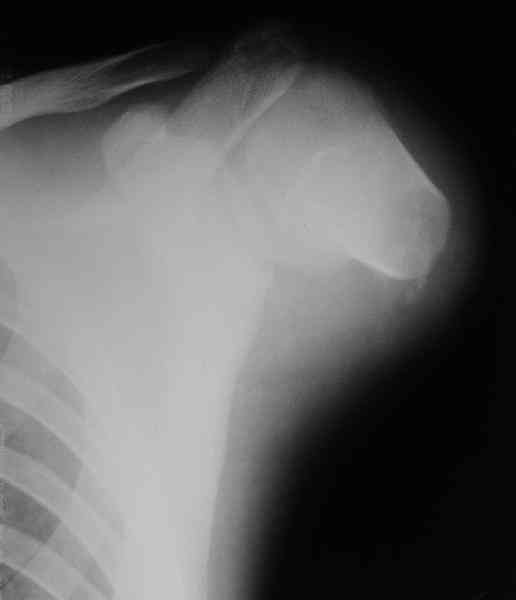

Здравствуйте, коллеги. Просьба помочь пациенту 17 лет.

Травма паровозная 4-го марта, формирование культи плеча в больнице по месту жительства.

К сожалению, даже за рубежом при такой короткой культе трудно делать протез. Можно посоветовать дистракционное удлинение для большего удобства адапторования протеза.